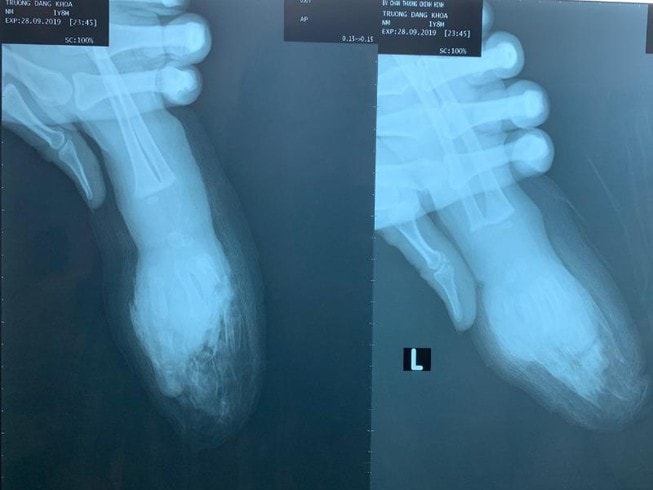

Người lớn sơ sẩy vài giây, bé trai 1 tuổi bị đứt lìa bàn tay

Bệnh viện Chấn thương chỉnh hình TP.HCM, cho biết bệnh viện vừa cứu bàn tay trái cùng bốn ngón tay đứt lìa cho bé trai 1 tuổi ở Đồng Tháp.